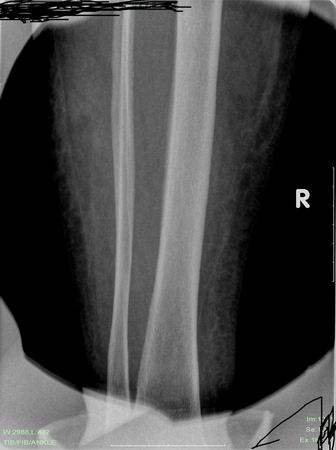

标题: X7094:肢端局部皮温增高、肿胀10天,我拷的一张正位像,请

皮下网状结构粗大模糊,软组织感染有,但骨质(-)。

时间表太短了,软组织广泛肿胀。必要时做mri可以发现早期骨髓腔和软组织改变。

骨质未见明显异常改变。  骨髓炎两周以后才会引起骨质改变,建议复查或ct检查。

右小腿软组织肿胀;右侧胫腓骨骨质未见明确异常。

建议:追踪复查。

胫骨外侧有骨膜增生,软组织明显肿胀,提示急性骨髓炎

只是软组织肿胀明显,要看早期骨髓病变还是mri好

软组织肿胀,但骨质结构未见明显异常,可抗炎治疗后复查或建议mri检查。

可以考虑早期骨髓炎,报正常也没错。

腓骨似有骨膜反应

软组织肿胀见粗大网状影,胫骨似有骨膜反应,提示急性骨髓炎。